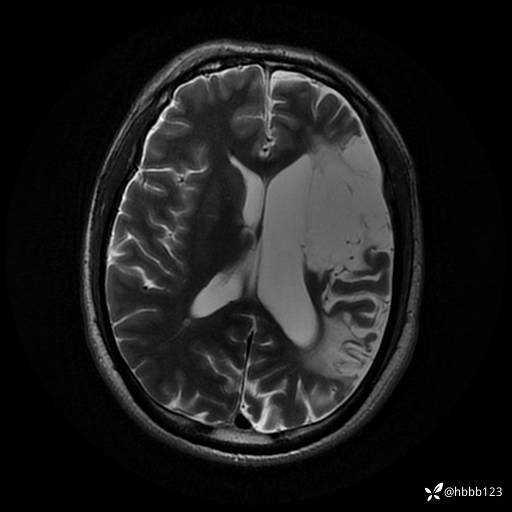

T2: